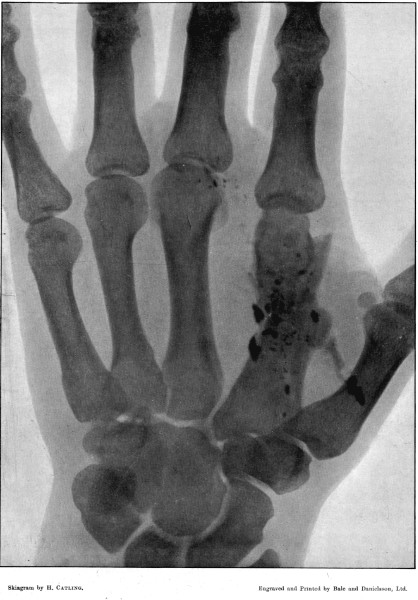

11. Fracture of the Metacarpus, showing Fragmentation of the Bullet194

12. Finely Comminuted Fracture of the Femur196

I am greatly indebted to my former colleague Mr. Cheatle for two of the illustrations of wounds, and for permission to quote some of his other experience, and to Mr. Henry Catling, to whose skill I owe the majority of the skiagrams of the fractures under my observation at Wynberg and elsewhere.